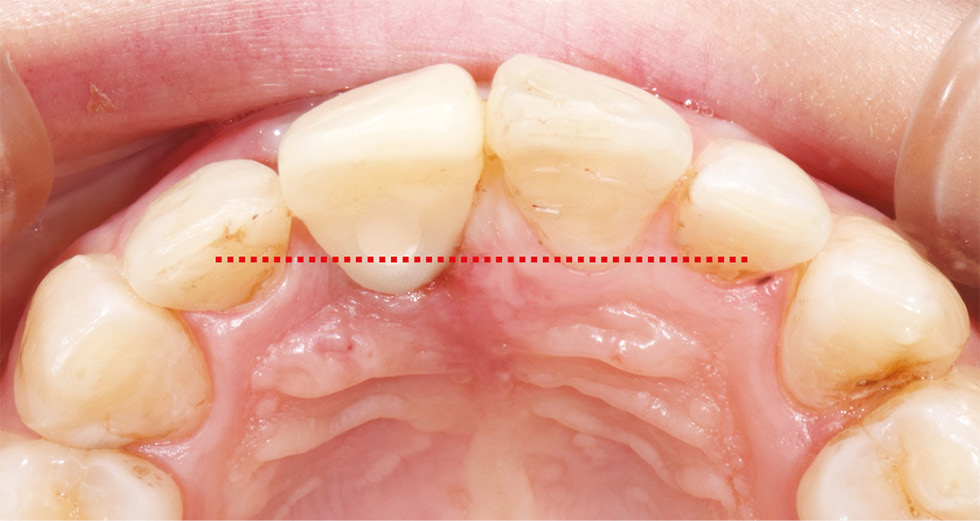

Еще одной сложностью с точки зрения протезирования является то, что на прямой имплантат, смещенный при установке к нёбной стенке, не всегда возможно изготовить эстетически приемлемый и анатомически правильный протез с винтовой фиксацией. Это связано с тем, что искусственная коронка будет более объемной, чем ранее удаленный зуб, за счет толщины конструкционного материала коронки (рис. 4, 5). Данное изменение анатомии гипотетически может приводить к дискомфорту пациента и нарушению некоторых функций (речи, жевания и др.).

Рис. 4. Прямой имплантат, фиксированный к небной стенке и объёмность коронки

Fig. 4. Direct implant installed more palatially, which results in a bulkier crown.

Рис. 5. Объемная коронка с нёбной стороны, не соответствую- щая индивидуальной анатомии.

Fig. 5. The bulkier crown on the palatal side is different from the individual anatomical form.